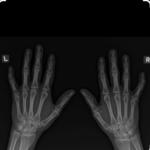

X-ray Both Hand AP & LAT

What is an X-ray Both Hand AP & LAT?

An X-ray of both hands AP & LAT is a type of imaging procedure that shows clear pictures of both hands. The anteroposterior frontal view and lateral side view serve to depict a general view of the hand bone’s structure and alignment while the lateral view views the side so that its depth and position of abnormalities can be detected. This X-ray is therefore usually used to diagnose fractures, joint damage, arthritis, infections, bone infections, problems concerning the growth plate, or congenital defects. The procedure is quick, painless, and non-invasive since it utilizes small amounts of radiation for the purpose of producing clear images that help the physician accurately diagnose and plan for any treatment of the diseased part of the hand.